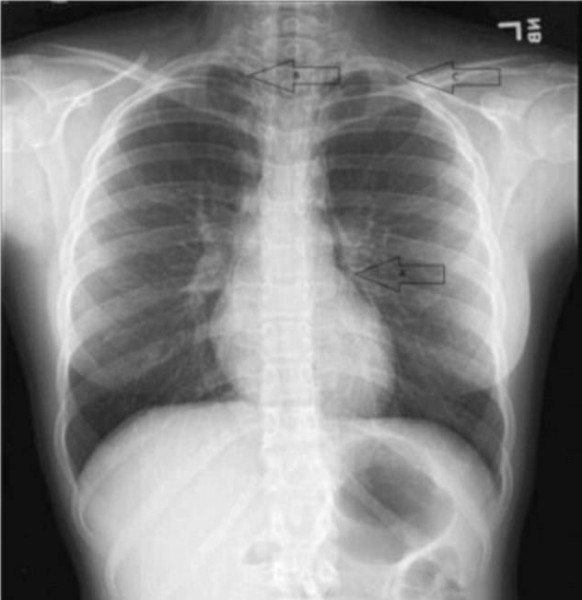

وفقا لما نشرته صحيفة "ديلى ميل" البريطانية، أصيبت الفتاة البالغة من العمر 16 عاما بانهيار في رئتيها بسبب تسرب الهواء منهما خلال الغناء بعدما اكتشفت في اليوم التالى أنها لا تستطيع التنفس، فاتجهت إلى المستشفى لإجراء الفحوصات وأخبرت الأطباء بصراخها المتتالى وغنائها في الحفل.